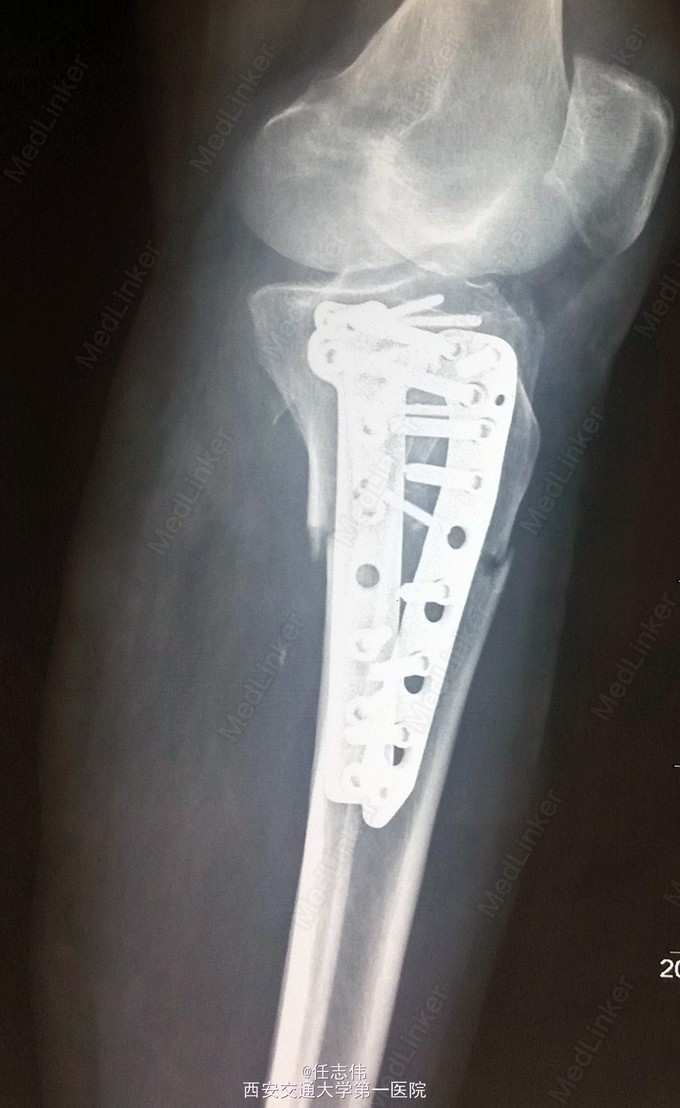

诊断:右胫骨平台骨折 处理:骨折切开复位内固定术。行内外侧入路钢板固定,术中行外侧平台塌陷复位,髂骨植骨内固定。另因考虑有后柱骨折,遂行后外侧切口,支撑钢板固定。术中见患者骨质疏松明显。 术后伤口愈合好,局部仍肿胀明显。